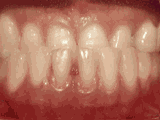

以下几种类型为典型的牙齿畸形症状,比如乳牙早失引起的前牙移位、牙齿错乱、牙列拥挤、上下牙齿开郃、深覆合、牙齿稀疏、前牙反颌地包天等,有的牙齿畸形还会导致脸型发育问题,出现小鸟嘴、弯月脸、短下巴、歪下巴、左右脸不对症等现象。

牙齿错乱表现为多生牙、牙床过小等造成,严重的拥挤错乱一般需要拔牙,给余牙移动的空间。

牙列拥挤主要常见牙齿过多,牙槽骨过窄,导致牙齿没有足够空间,一般根据检查结果,除了拔牙还有片切、扩弓、推磨牙远移等方法,不见得一定要拔牙。